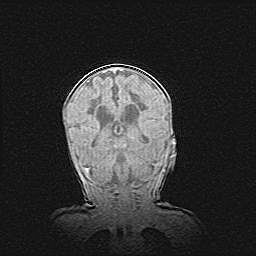

Лейкомаляция с кистозно-глиозной дегенерацией головного мозга.

Возраст: 2 месяца 25 дней

Вес: 6400 г

Окружность головы: 40 см

Срок гестации: 41 неделя

Лейкомаляцию относят к ишемически-гипоксическим повреждениям головного мозга, диагностируемым у новорожденных. При лейкомаляции в головном мозге обнаруживают очаги некроза, возникшие после тяжелой гипоксии и нарушения кровотока. В процессе морфогенеза очаги проходят три стадии: 1) развития некроза, 2) резорбции и 3) формирования глиозного рубца или кисты. Перивентрикулярная лейкомаляция (ПЛ) встречается примерно в 12% случаев среди новорожденных, обычно – у недоношенных детей, причем, частота ее зависит от массы, с которой младенец появился на свет. Наибольшее число малышей страдает лейкомаляцией, если масса при рождении 1500-2500 г.